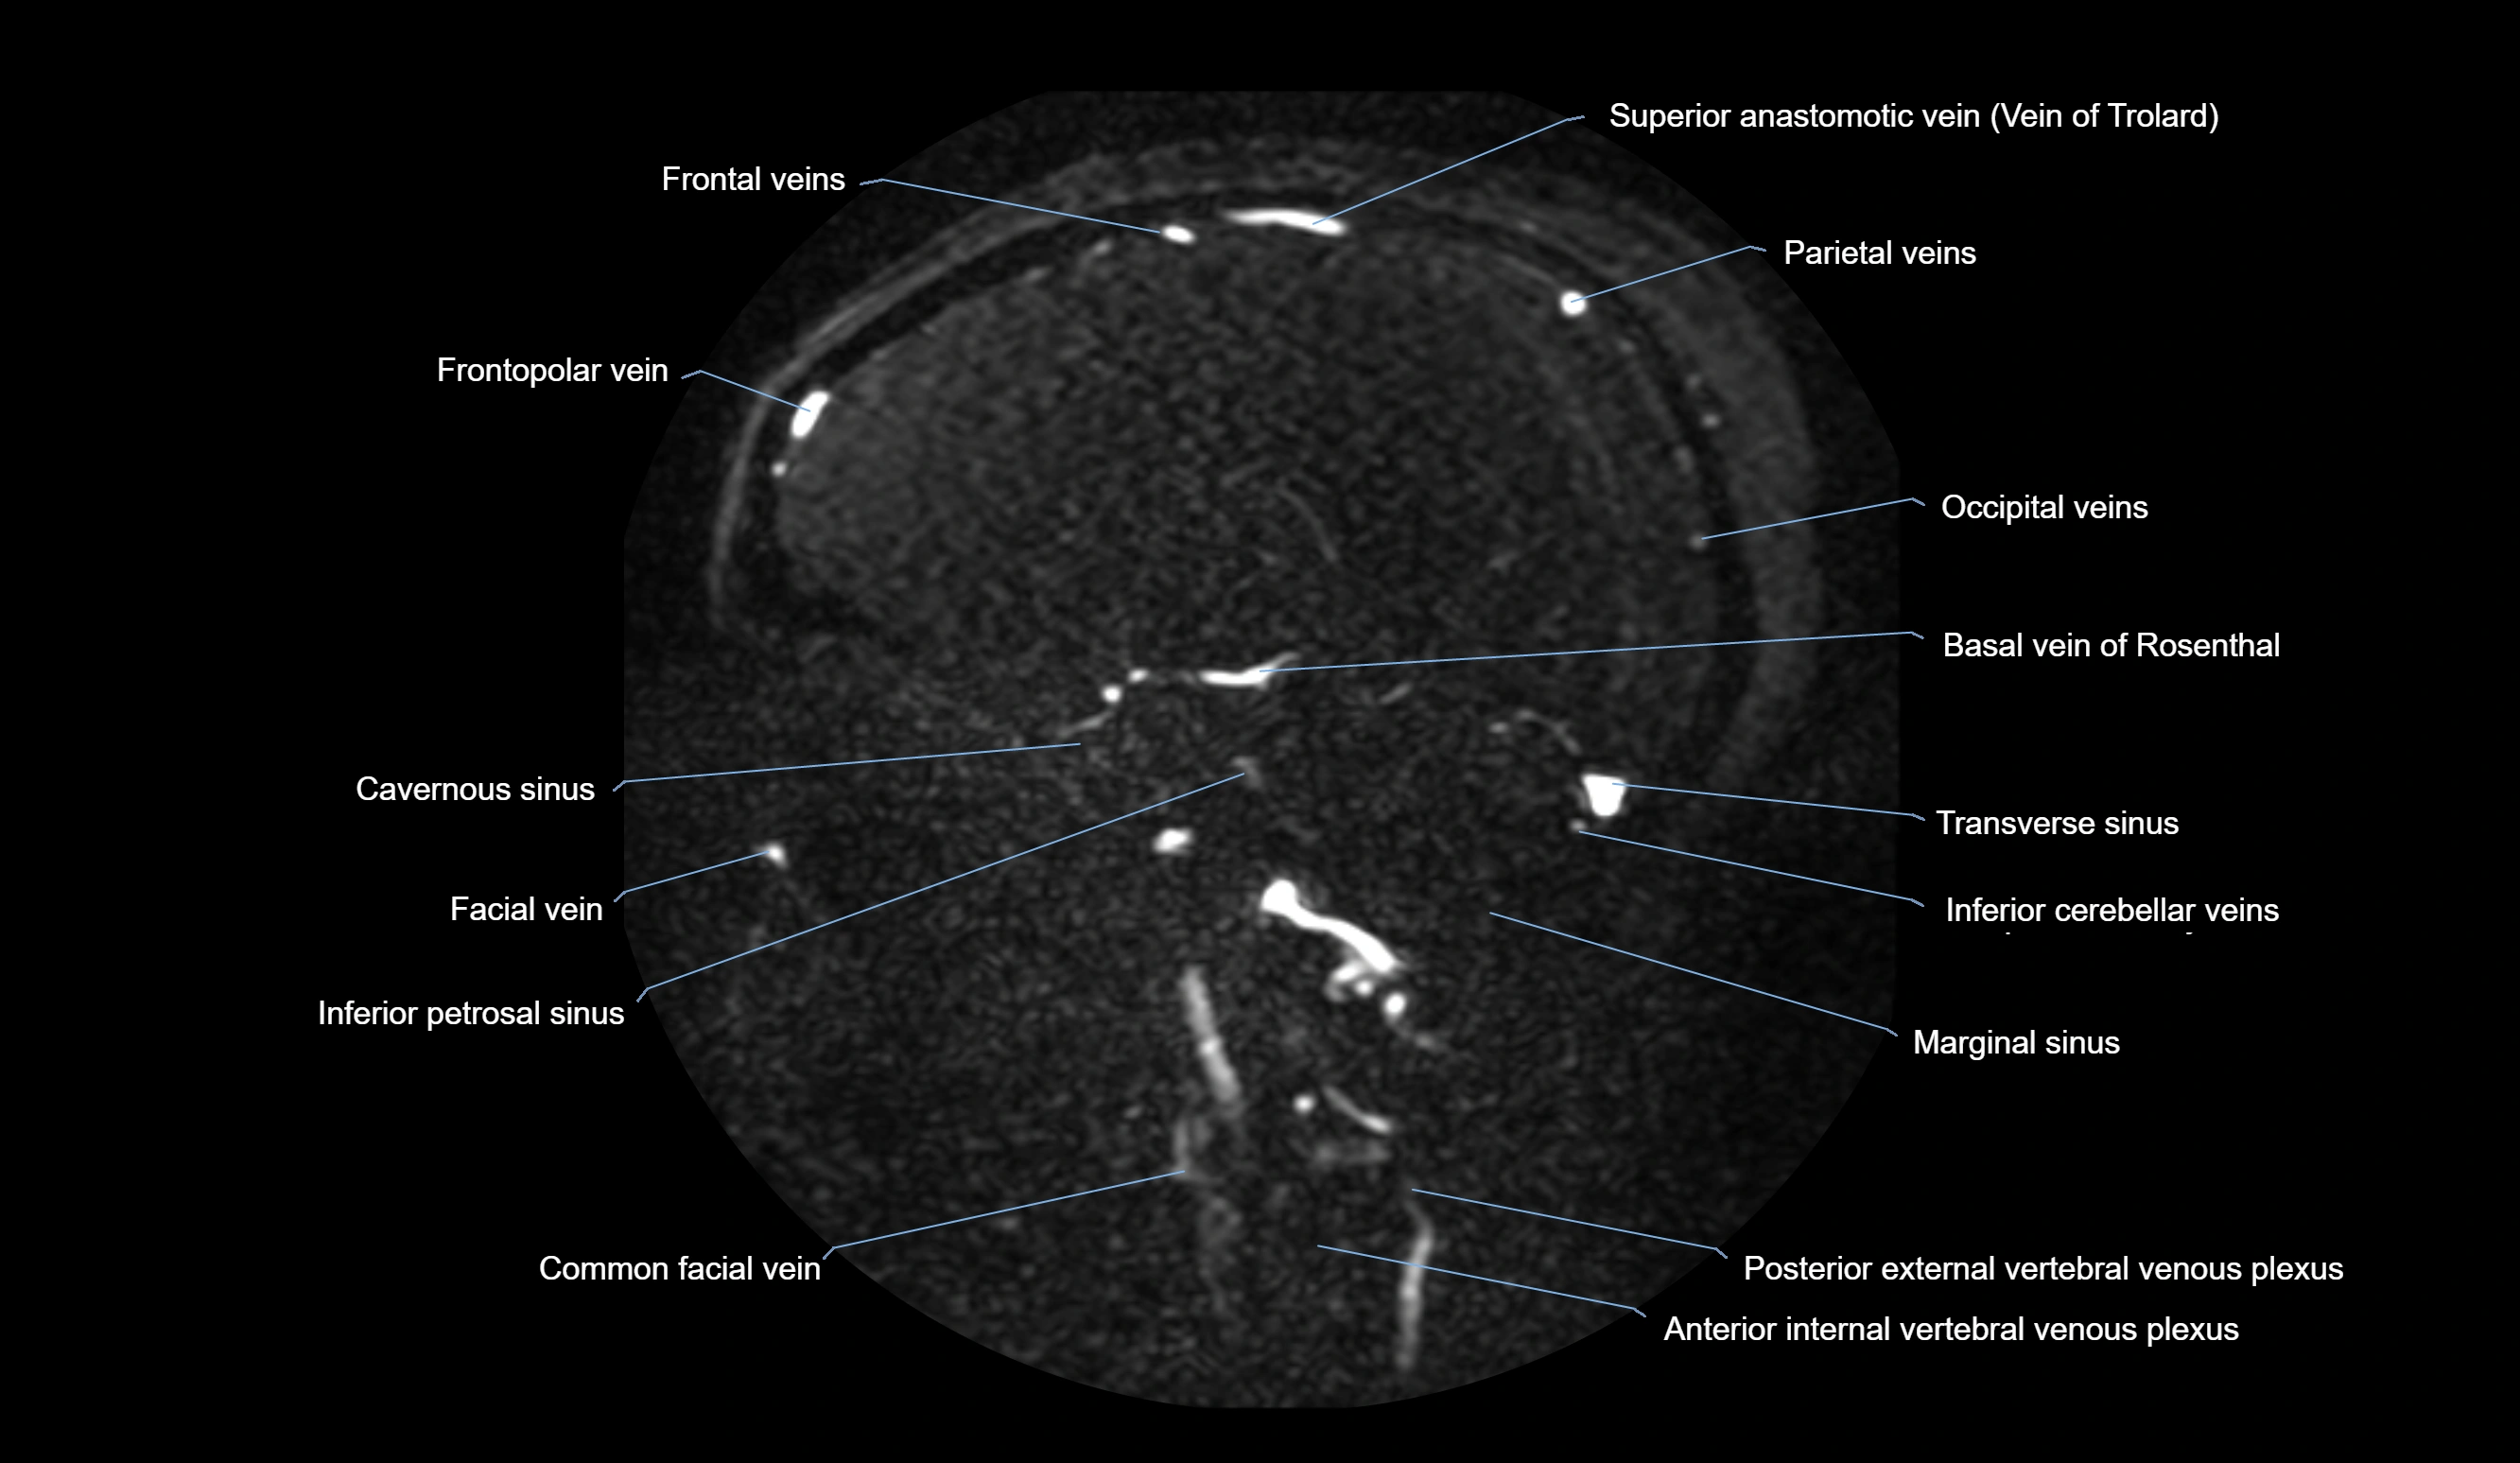

MR Venography (MRV):

• Time-of-flight (TOF) or contrast-enhanced MRV shows the angular vein as a bright enhancing venous channel

• Clearly demonstrates its continuity with the facial vein and superior ophthalmic vein

• MRV is highly useful in evaluating thrombosis, venous obstruction, or collateral venous drainage